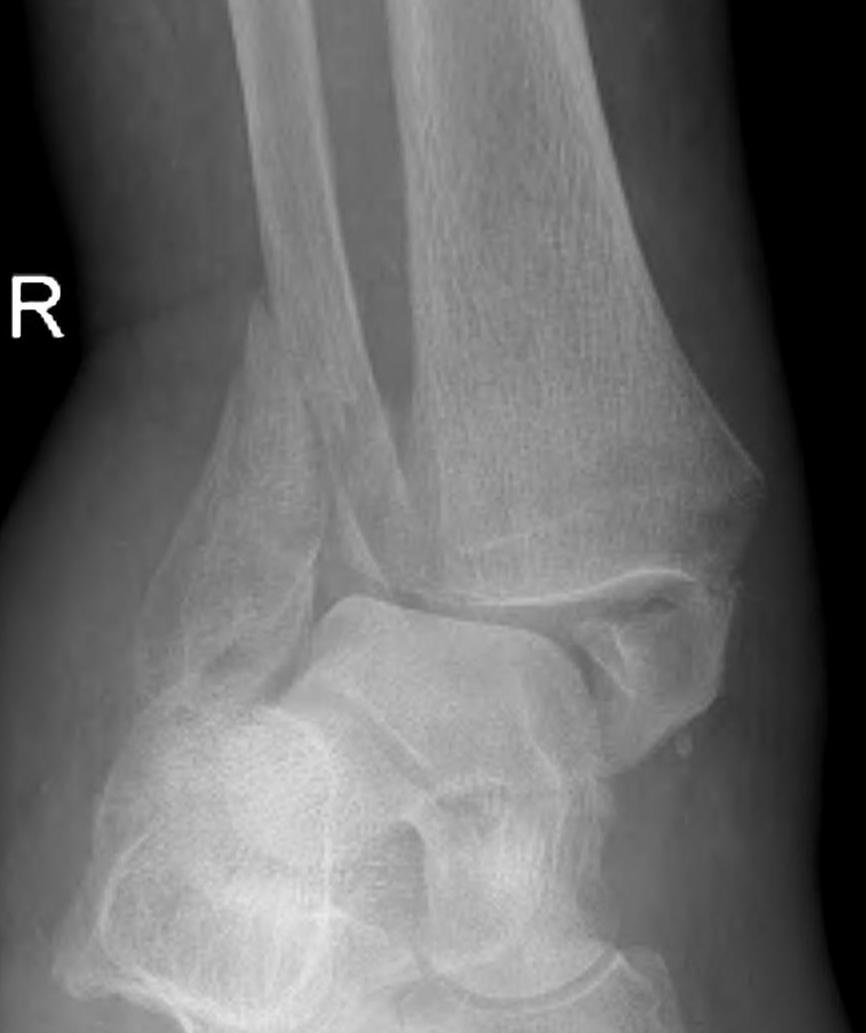

Issues

Poor bone

Poor skin

Poor wound healing

Poor union rates

ORIF

- poor bone stock

- wound issues